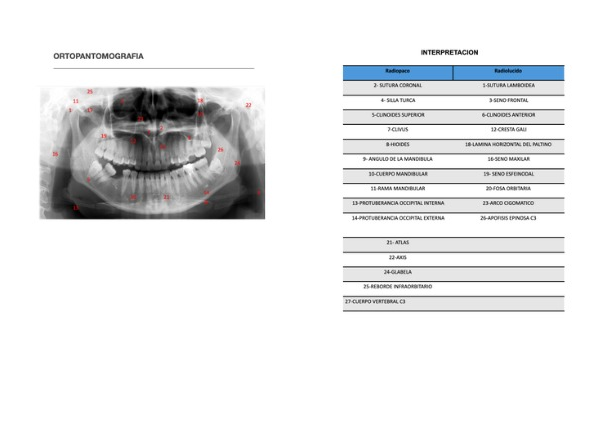

revista radiologica RADIOLOGIA- CALIXTO ALFARO JOSE LUIS | Page 25

revista radiologica RADIOLOGIA- CALIXTO ALFARO JOSE LUIS | Page 24

revista radiologica RADIOLOGIA- CALIXTO ALFARO JOSE LUIS | Page 26